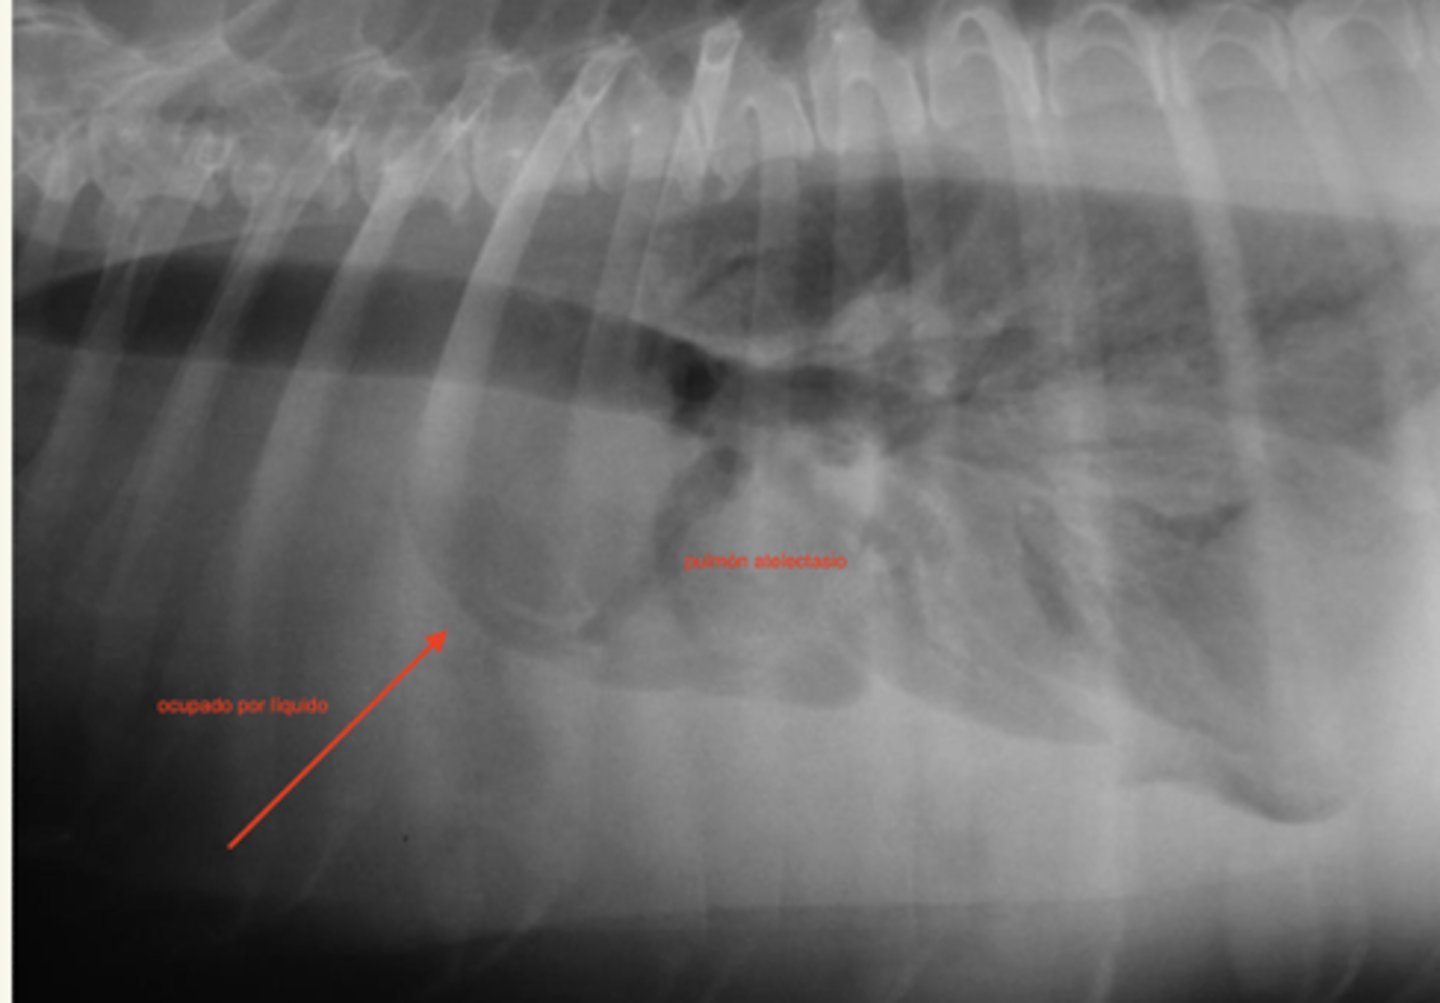

efusión pleural

patología: